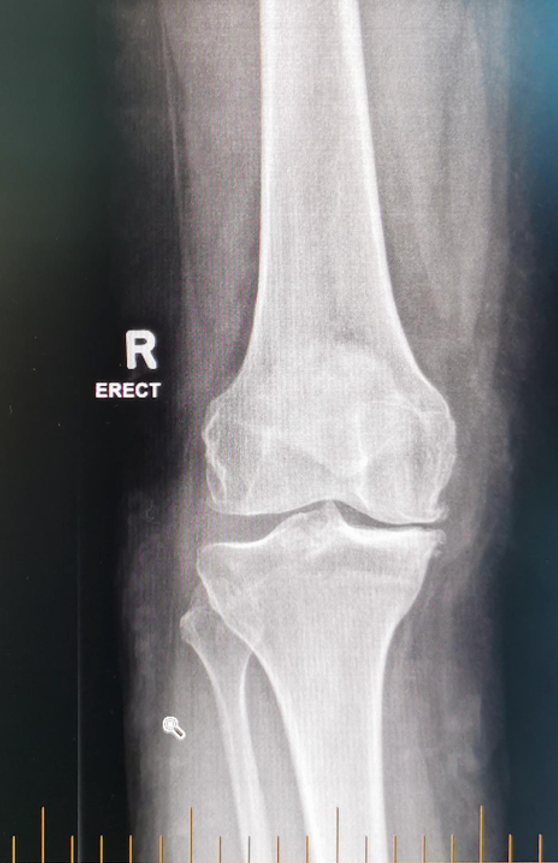

Ligament Injuries (Knee Instability)

Ligaments are strong bands of tissue that help keep your knee stable. If one of these ligaments tears, your knee may feel unstable, buckle, or give way, especially when walking or playing sports. Over time, this instability may also damage other tissue in your knee such as your cartilage or meniscus. The anterior cruciate ligament (ACL) is commonly injured, often due to a sudden twisting motion or landing awkwardly, while the posterior cruciate ligament (PCL) is usually torn from a direct impact, such as a fall or car accident. Injuries to the medial collateral ligament (MCL) and lateral collateral ligament (LCL) occur when there is force applied to the inner or outer knee. More severe cases involve multiple ligament tears, often due to high-impact trauma, or in patients with high BMI taking a wrong step. While minor injuries may heal with rest and rehabilitation, complete ligament tears often require surgery to restore stability and function. (READ chapter on ACL injuries for primary care professionals)